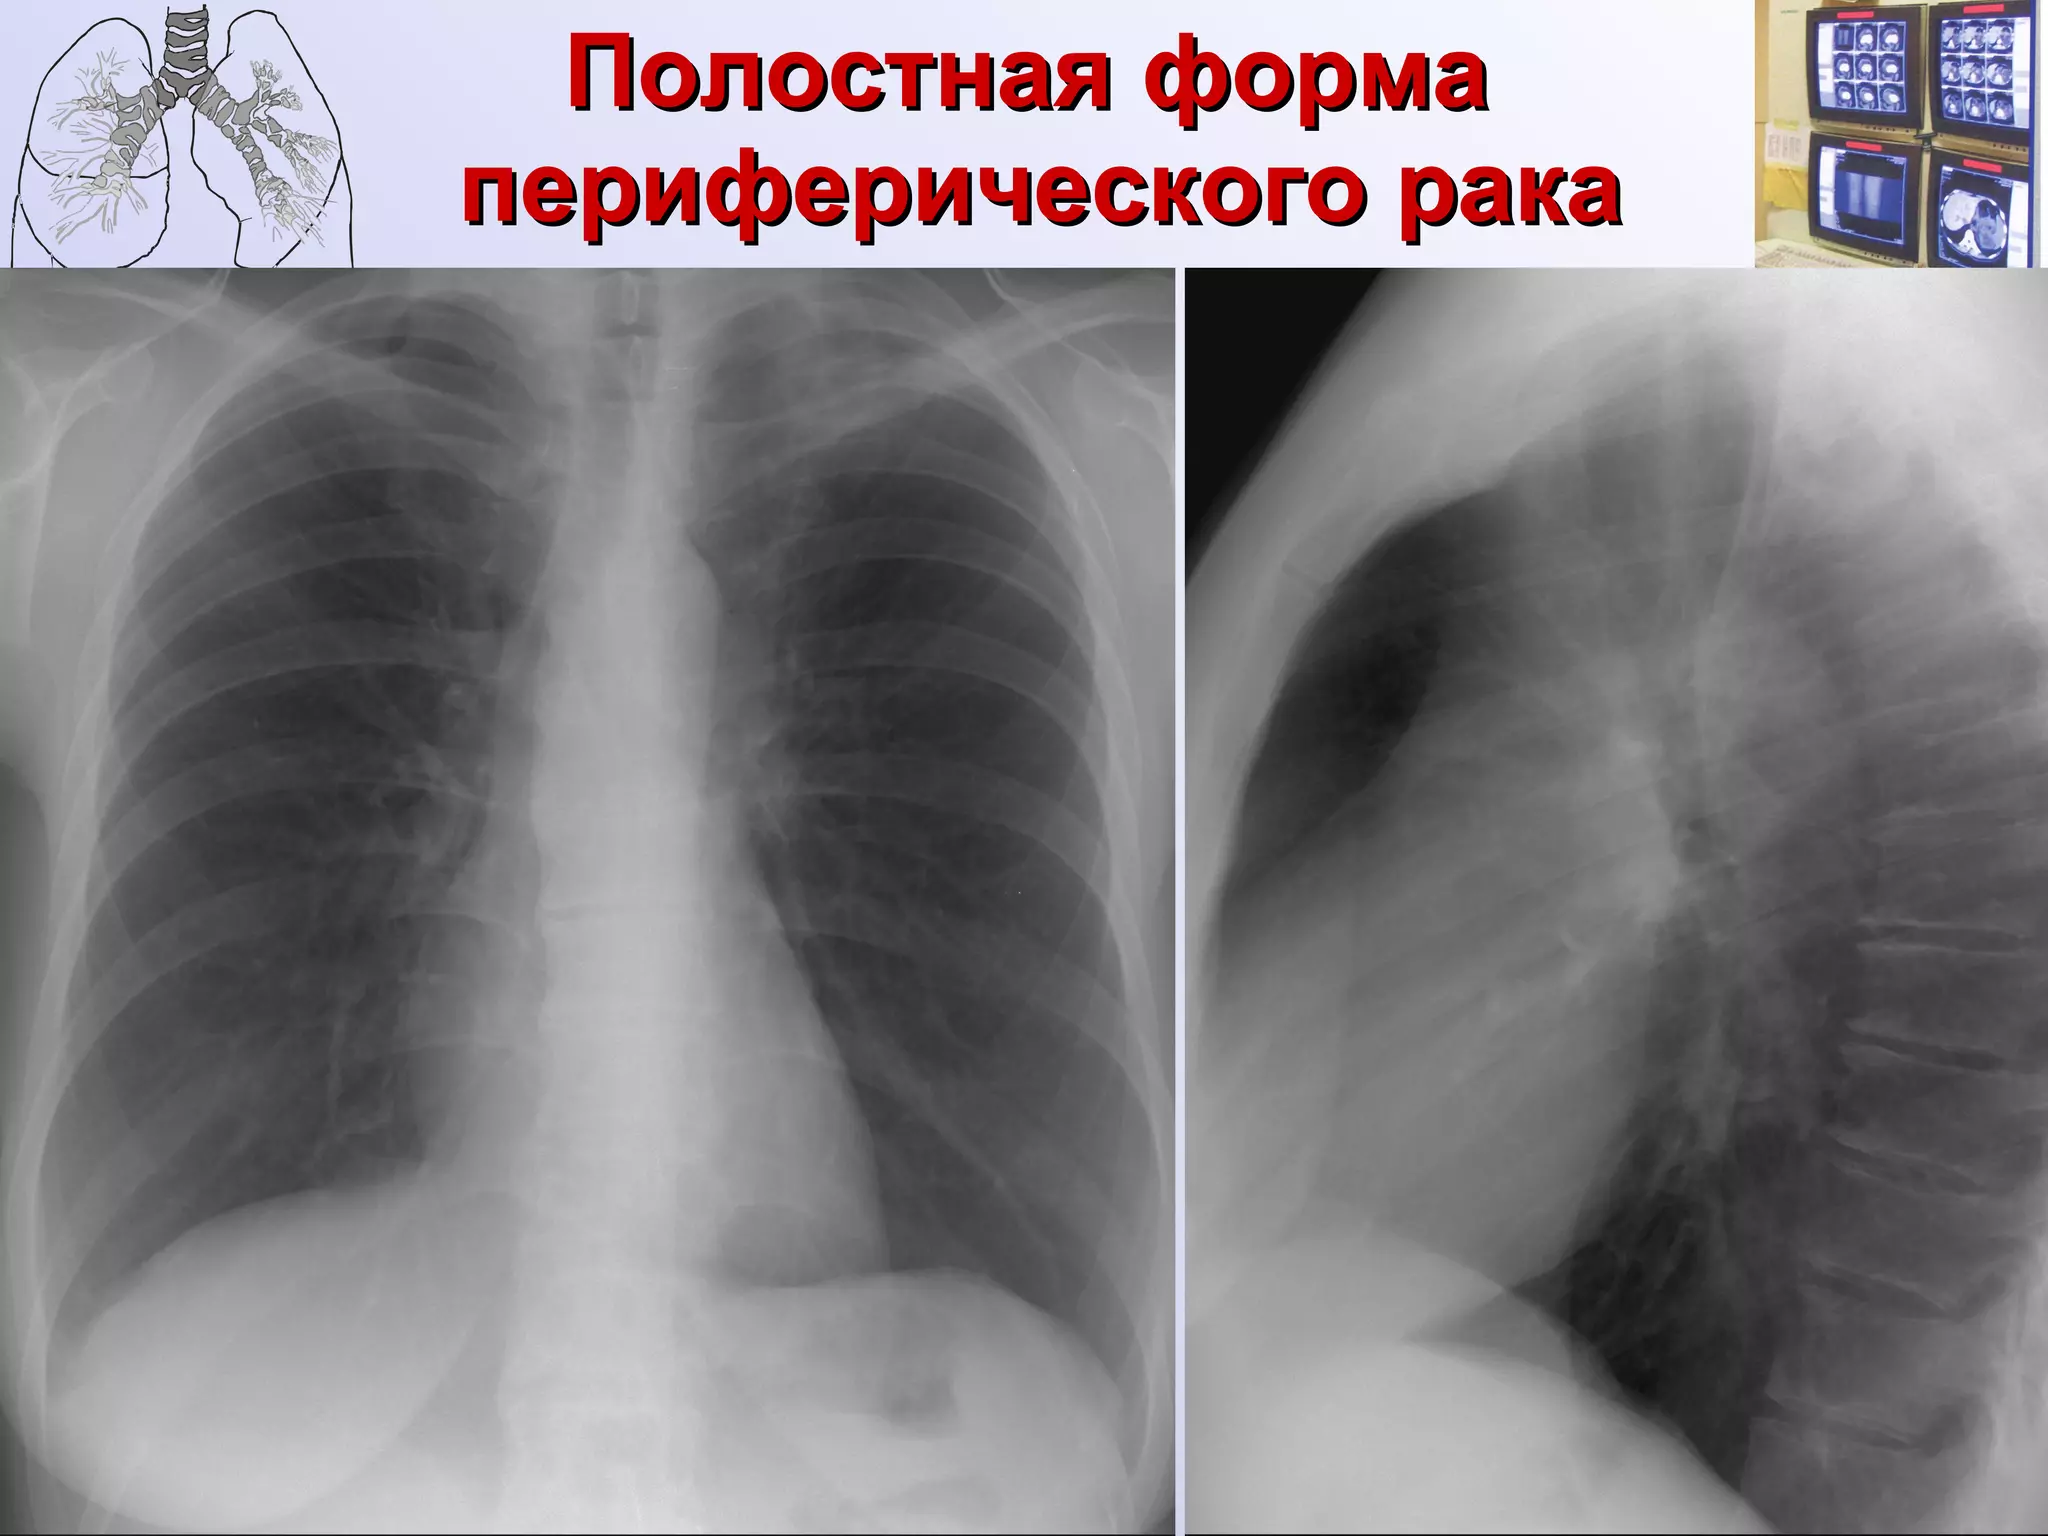

Полостная форма  периферического рака

Полостная форма  периферического рака Контуры неровные, полициклические. Полость расположена центрально или эксцентрично. Толщина стенок неравномерная. Внутренний контур неровный, бугристый,  бухтообразный. Окружающая легочная ткань мало изменена.